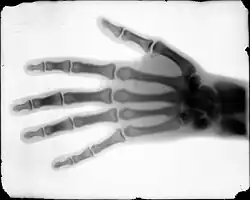

In 1895, Buckwalter took interest in X-ray technology, after its discovery by professor Wilhelm Röntgen earlier that year. Sponsored by the Rocky Mountain News, Buckwalter partnered with physician C. E. Tennant and the Homeopathic Medical College of Denver on a series of X-ray photograph experiments. For the experiment Buckwalter produced X-ray tubes locally using leaded glass which was previously thought to be unsuitable, but the experiment proved that leaded tubes could produce a clear image.[6] The X-ray images were the first produced in the American West and among the earliest in the country.[1][7]

After the Rocky Mountain News published the results of the experiment, Buckwalter and Tennant were contacted by attorneys Ben Lindsey and Fred W. Parks to examine a client in a malpractice lawsuit with the new technology. The lawsuit represented James Smith, who had fractured his leg after falling from a ladder. He was examined by Dr. W.W. Grant, who misdiagnosed the fracture, insisting the leg was merely stiff. Instead of immobilizing the limb he prescribed exercises which exacerbated the injury. Case number 24159 was heard in the District Court of Arapahoe County (now Denver) on December 2, 1896, by Judge Owen Le Fevre, who allowed Buckwalter and Tennant to testify as expert witnesses and present their findings. The defense objected unsuccessfully to the court, arguing X-rays were the "testimony of a ghost". The X-rays along with the testimony of Buckwalter and Tennant proved that there was a fracture in the leg. The landmark case marked the first time that X-ray evidence was admitted into a court of law.[8]